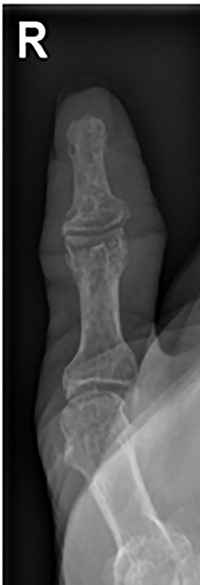

Her blood tests on presentation were unremarkable and X-rays of her right thumb showed a lytic lesion involving the tuft of the distal phalanx (Figs. 4 and 5). She was admitted to the hospital and was treated as having an infection of her right thumb with elevation and intravenous antibiotics. She underwent emergency surgery the next day for a washout and debridement of the right thumb. During the debridement in theatre, there was no pus in the pulp, but the bone was found to be eroded and soft, thus multiple specimens from the bone were sent for microscopy, culture and sensitivity, acid-fast bacilli (AFB) and histopathology.

AP radiograph of right thumb showing erosion of tip of distal phalanx.

Lateral X-ray of right thumb showing erosion of tip of distal phalanx and soft tissue swelling.